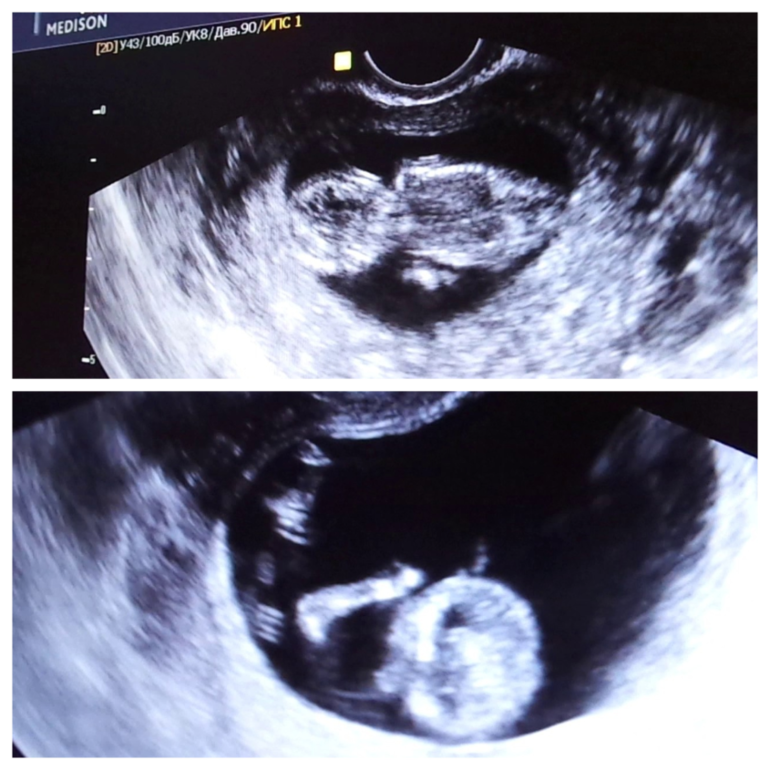

У нас было уже 5 УЗИ (одно из них скрининг) и это таааакое наслаждение видеть своих пупсиков!) на последнем они дрались друг с другом:) Так что надеюсь все-таки мальчишки)))

А вот и мы:

Мне кажется, или у нашего пупсика, что сверху попец что надо?